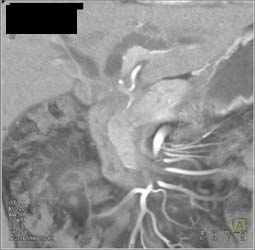

Diagnosis

Hepatoma